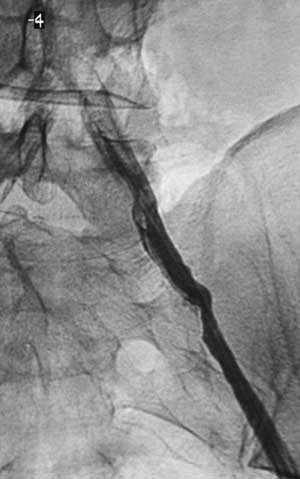

Имплантация артериального стента Белорусского производства.

Рис. 4. Контрольная артериограмма после предилатации.